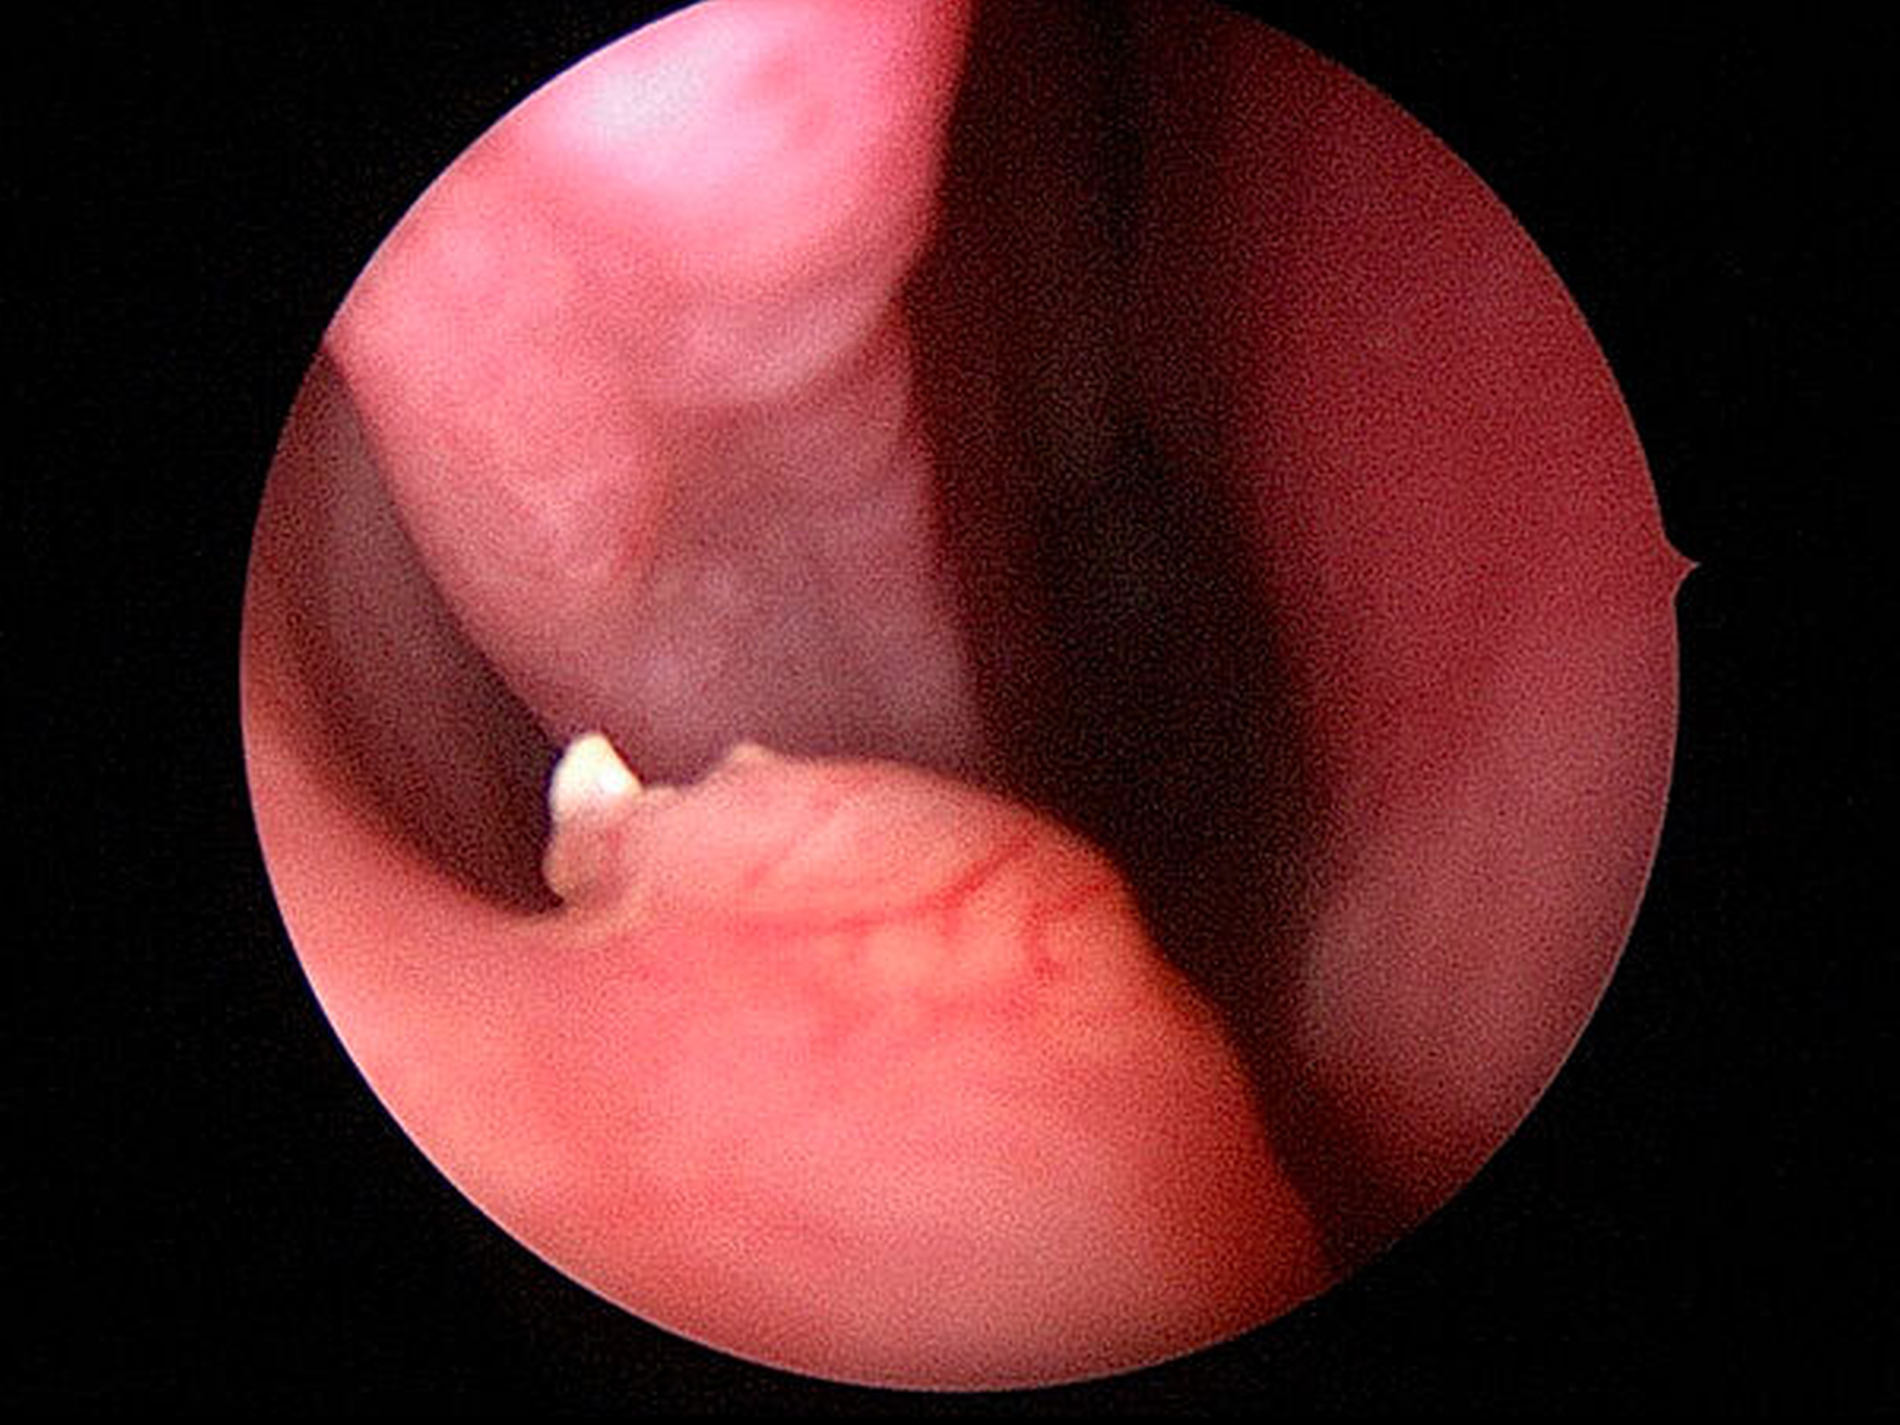

In allgemeiner Schmerzausschaltung wurde endoskopisch unterstützt eine Infundibulotomie mit nachfolgender Kieferhöhlenrevision und transnasaler Entfernung des Zahns 13a aus dem rechten Nasenboden durchgeführt (Abbildungen 3a bis 3c). Der postoperative Heilungsverlauf war komplikationslos, die definitive Histologie des entnommenen Kieferhöhleninhalts bestätigte die Verdachtsdiagnose einer chronischen Sinusitis maxillaris.